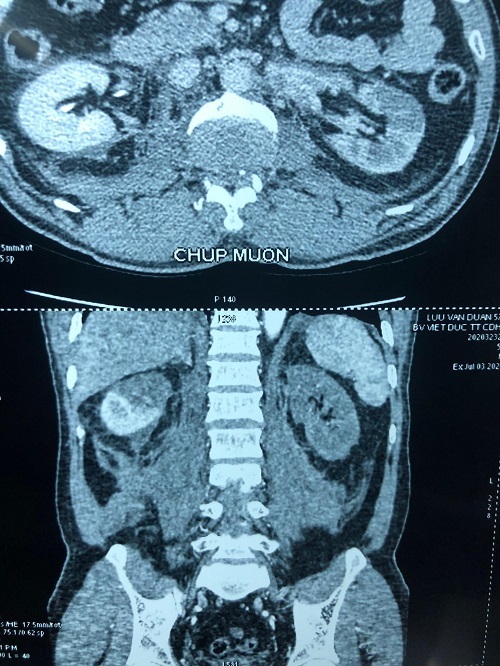

Thực hiện chụp chiếu, các bác sĩ phát hiện thận bên phải người bệnh có huyết khối động mạch cực trên, mất phần cấp máu cho cực trên, thận bên trái thiếu máu hoàn toàn, chức năng thận giảm, có biểu hiện suy thận.

| Phim trước mổ của người bệnh, thận phải mất 1/2 chức năng, thận trái mất hoàn toàn. Ảnh: BVCC |